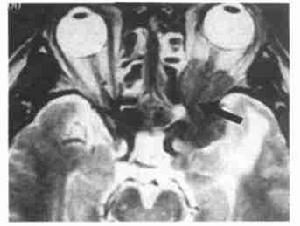

头颅CT检查可了解肿情况。

早期x线摄眼眶可能无变化,晚期则可有眼眶扩大和(或)伴有质破坏。